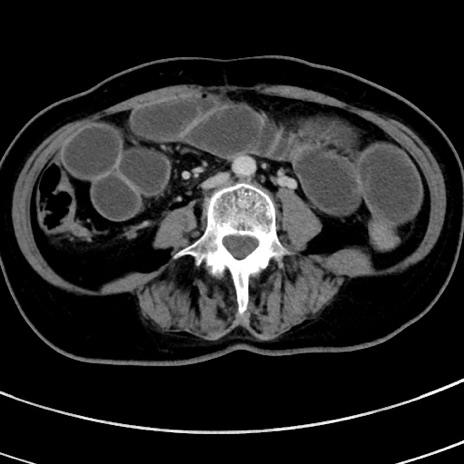

症例9(横断像)

【症例】 60歳代女性

【主訴】むかつき、みぞおちの痛み

【現病歴】3日前よりむかつきがあり、食事がとれない。

【既往歴】糖尿病

【身体所見】発熱なし、心窩部圧痛軽度あるも、腹膜刺激症状なし。

【データ】WBC 7400、CRP 1.92